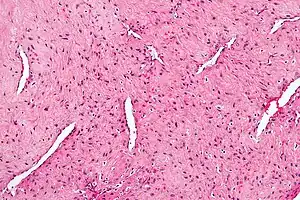

Micrograph of a nasopharyngeal angiofibroma H&E stain.

Nasopharyngeal angiofibroma, also known as juvenile nasal angiofibroma, is a non-cancerous, locally aggressive vascular tumor of the nasopharynx.[3]

If nasopharyngeal angiofibroma is suspected based on physical examination (a smooth vascular submucosal mass in the posterior nasal cavity of an adolescent male), imaging studies such as CT or MRI should be performed. Biopsy should be avoided as to avoid extensive bleeding since the tumor is composed of blood vessels without a muscular coat.